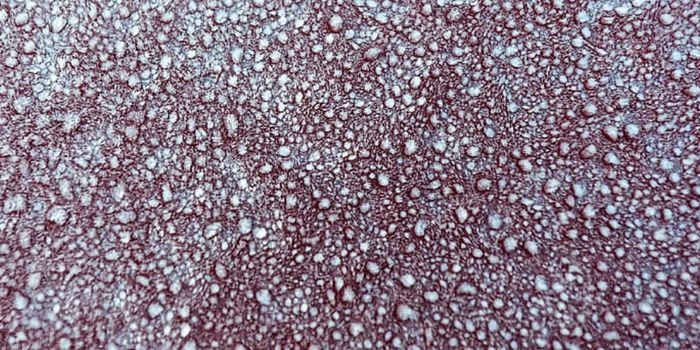

JUL 21, 2021MicrobiologyBlood culture is the most widely used diagnostic tool for the detection of bacteremia and fungemia. It is the most impor ...